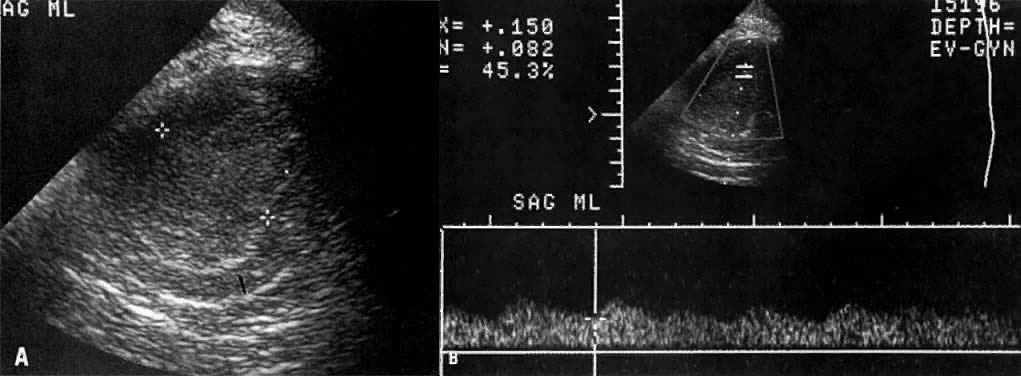

Fig. 21. Stage IA endometrial carcinoma. A. Sagittal TVUS image of the uterus shows marked, inhomogeneous endometrial thickening (between asterisks). Note preservation of the myometrium ( arrow ). B. Spectral Doppler waveform obtained from the endometrial mass shows a low resistive index suggestive of malignancy.

Submucosal fibroids and intrauterine hematomas may also have a hyperechoic appearance that may simulate endometrial carcinoma. The less frequently encountered hypoechoic pattern of endometrial carcinoma can be differentiated from that of intramural fibroids by the association of variable degrees of shadowing with the latter. Other suggestive but nondiagnostic signs of uterine malignancy are a rapid increase or any postmenopausal increase in the size of a uterine mass, extrauterine extension, and coexistence of a uterine mass with abdominal metastases.52 Spectral and color Doppler can enhance the ability of ultrasound to make a more specific diagnosis. Although no flow will be demonstrated in blood clots, high-resistivity flows are typically seen in benign disease compared with low-resistivity flows seen in endometrial carcinoma (Fig. 21B). However, some overlap exists between the Doppler findings of the two disease groups. Endometrial carcinoma may occasionally obstruct the uterus, causing variable degrees of pyometra, hydrometra, or hematometra.